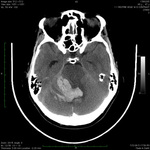

Tomografia computadorizada do cérebro mostrando hemorragia no cerebelo com extensão para o quarto ventrículo

Do acervo de Dr. S. H. Subramony; usado com permissão